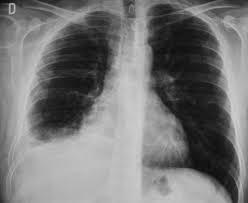

2. Imagenología

1. Desplazamiento hacia afuera del vértice del diafragma

1. con una pendiente súbita hacia el surco CF

1. Separación > 2cm entre la búrbuja de aire gástrica y pulmón

2. RX

1. Lateral

1. 75-100 mL acúmulo en surco costofrénico- POST-> visible

2. PA

1. 175-200 ml surco CF Lateral --> deliniarse imagen frontal